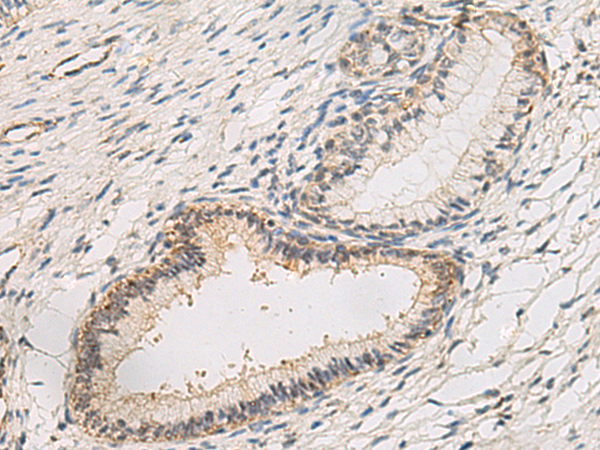

分类: 科研抗体货号: P02882别名: LMP10; MECL1; beta2i应用: WB,IHC反应种属: Human, Mouse, Rat